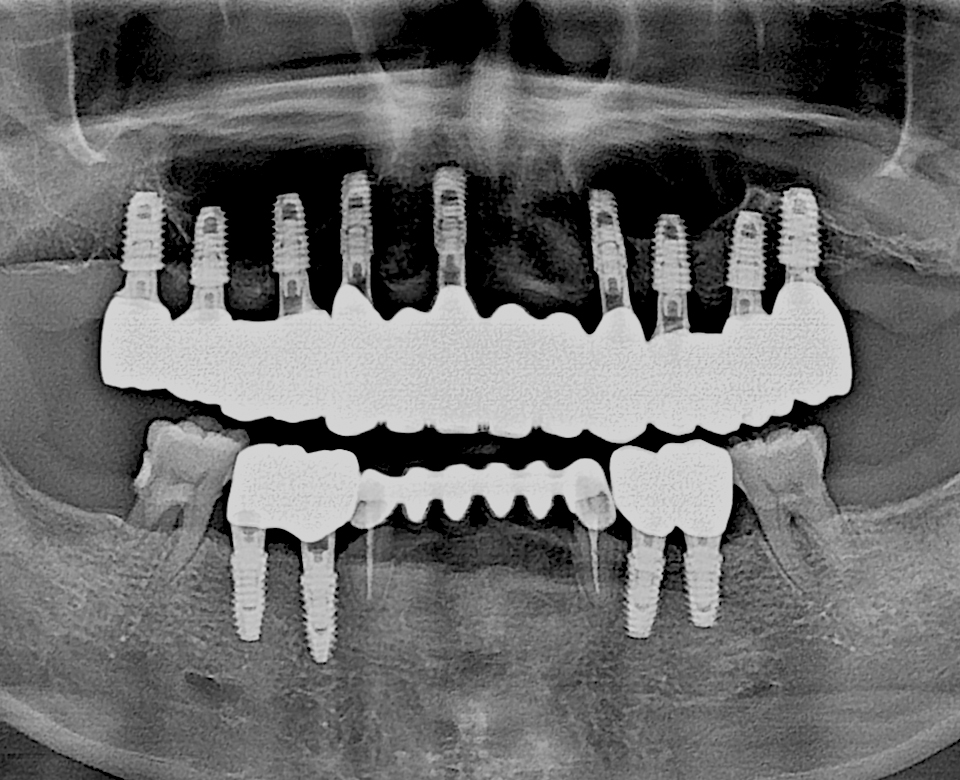

전체 임플란트

틀니 없이 편안한 치아

전체 임플란트는 1,2개의 임플란트와는 다른 난이도가 높은 수술입니다.

단순 치아가 아닌 전반적인 구강구조의 해부학적 의학지식과 풍부한 임상경험이 필요합니다. 또한 최소한의 오차범위로 정밀한 치료를 위한 정확한 분석과 기술력이 뒷받침되어야 합니다.

전체 임플란트란?

전체 임플란트는 치아가 대부분 또는 하나도 남지 않고 상실된 경우로

상실된 치아 전체를 회복하는 시술방법을 말합니다.

난이도 높은 시술이기 때문에 숙련된 전문의의 임상경험을 바탕으로 교합에 대한 정확한 이해와 기술력이 필요합니다.